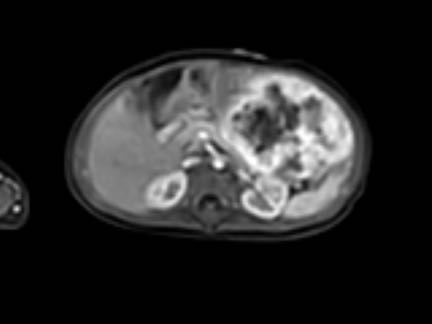

Hình ảnh MRI của một bé gái chín tháng tuổi có khối u ở bụng trái. MRI cho thấy khối u tuyến thượng thận trái, một phần đặc, một phần nang. Có nhiều di căn gan.

Khối u đã được sinh thiết. Có tình trạng chảy máu liên tục qua kim dẫn đường. Vào cuối thủ thuật, hai nút bọt gelatin đã được đặt vào (các dải tăng âm (mũi tên)).